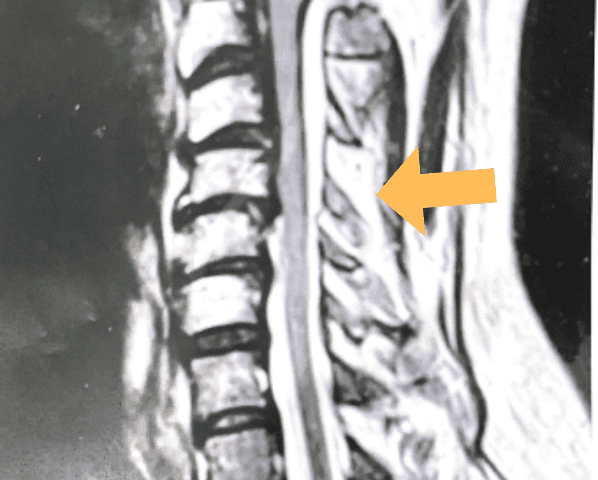

This 57 year-old male presents with severe neck, left shoulder and arm pain and weakness in his hand since being involved in a motor vehicle accident nine months prior. The patient had subsequent left shoulder surgery although he still complained of pain postoperatively and his weakness persisted. He was on no blood thinners. He underwent imaging. The cervical spine MRI revealed an extensive dorsal epidural collection from C1-2 through C5 with associated spinal cord compression. In addition there were multisegmental degenerative changes with foraminal stenosis worse at C4-5 (Fig. 1a and 1b).

(1a) Sagittal and axial T2-weighted cervical MRI demonstrating extensive dorsal epidural collection with hyperintense signal consistent with fluid causing spinal cord compression.

(1b) Hyperintense signal (arrow) at the C3-4 interspinous space consistent with ruptured interspinous ligament,C4-5 (Fig. 1a and 1b).

The fluid was possibly consistent with CSF versus chronic hematoma. The patient was also noted to have a high signal within the interspinous space of C3-C4. This high signal was consistent with a ruptured C3-4 interspinous ligament. Cervical flexion-extension x-rays demonstrated 6 mm of widening of the C3-4 interspinous space on flexion x-ray consistent with cervical instability (Fig. 2a and 2b).